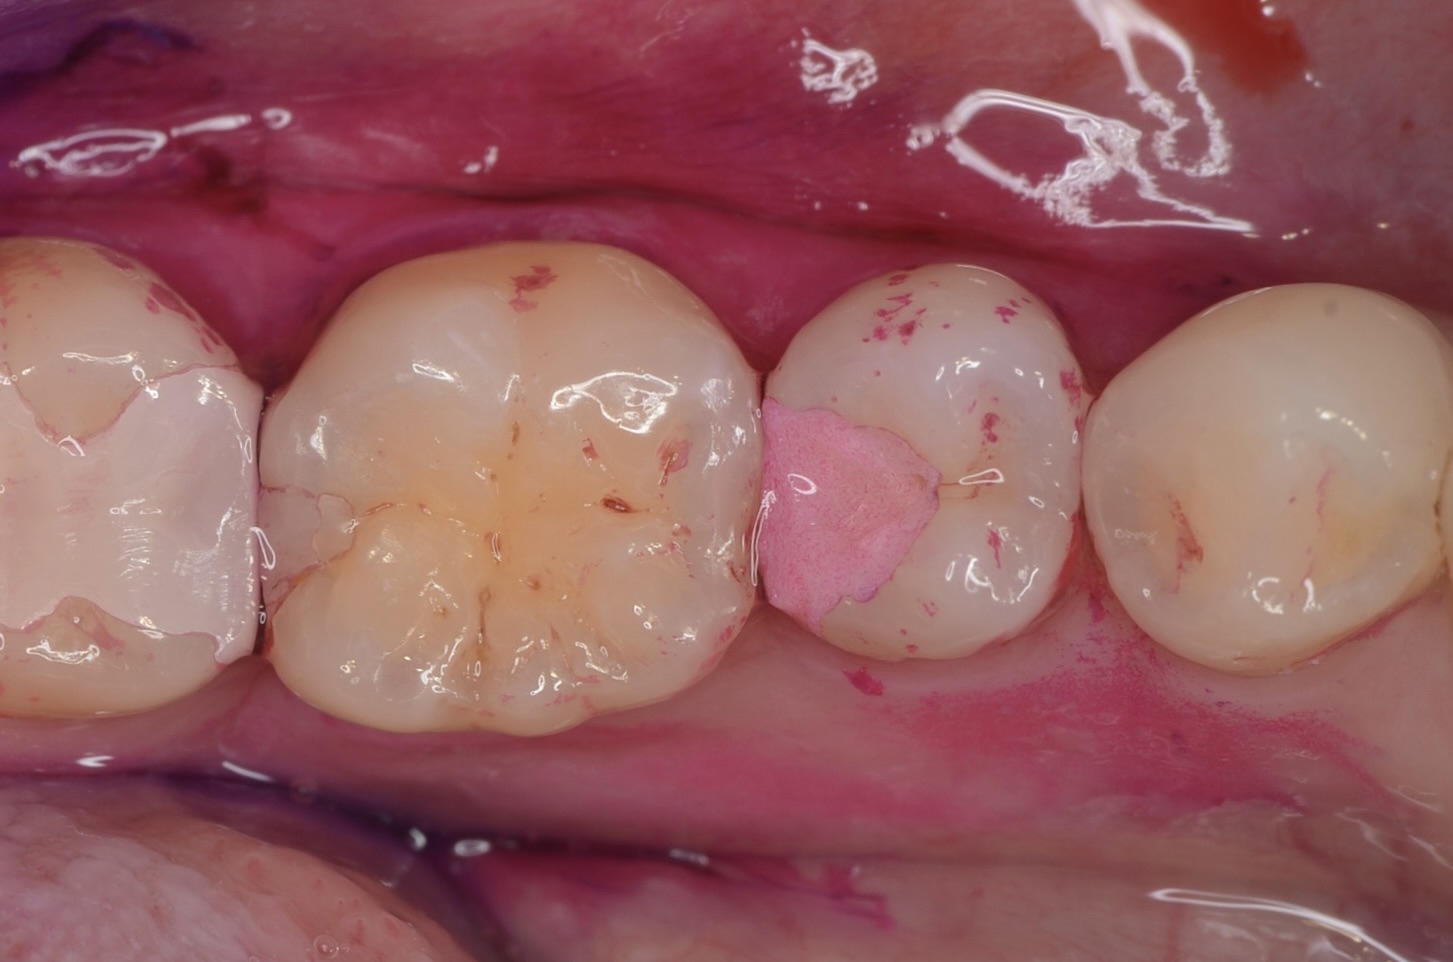

歯垢の染め出し

歯垢は接着操作を妨げます。治療前には、必ず歯垢染め出し液により歯垢を見える化し、その後ジェットパウダークリーニングにより徹底的に除去します。保険診療ではここまでする事はほとんどありません。 -